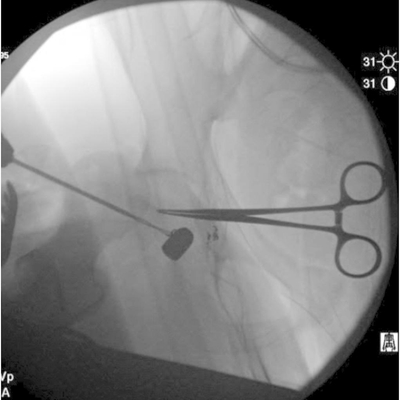

Click on an image below to view more info.